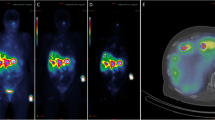

Quantitative SPECT images

Figure 1 shows the post-filtered SPECT/CT images exemplarily for patient 3. In addition, the PET/CT performed 2 weeks prior to treatment is shown as the diagnostic gold standard.